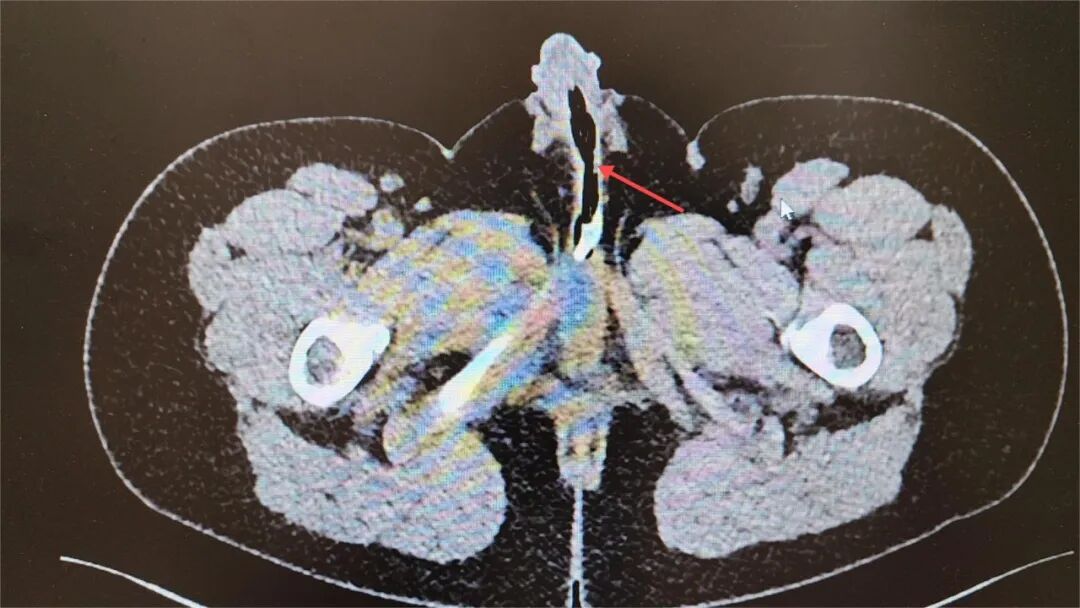

检查结果让在场的医生也不禁一愣,一坨管子折叠堆积在小汤的尿道内,看样子还不短。

为避免异物对泌尿系统造成进一步损害,泌尿外科副主任颜加强、主治医师李飞在尝试了多种体外拔除的方法未果后,最终使用小儿输尿管镜,从男孩尿道进入尿道内,用异物钳完整取出了长约66厘米的塑料管。术后,小汤恢复良好,近日已顺利出院。